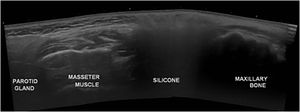

A 58-year-old woman presented to the dermatology clinic with an eight-year history of recurrent facial swelling. The patient's symptoms started after receiving cosmetic filler injections in the face with an unknown material by a general practitioner. At the initial examination, the patient presented with painful facial edema, erythema, and the presence of inflammatory subcutaneous nodules in the cheeks and lips (Fig. 1). The patient had received treatment with methotrexate and hydroxychloroquine for 2-years, colchicine for 1-year, and antibiotics, including doxycycline and minocycline, for 6-months without improvement. She had been employing intramuscular dexamethasone every two weeks for more than five years with irregular control. Skin biopsies showed a chronic inflammatory infiltrate composed of histiocytes and lymphocytes. Abundant translucent micro-vacuoles of silicone-like material were found inside the histocytes. Histopathology was consistent with a foreign body granuloma (Fig. 2). Ziehl-Neelsen, Gram, and PAS staining were negative. The histocytes were CD68 positive and S-100 negative. Skin biopsy cultures for bacteria, mycobacteria, and fungi were performed twice. All cultures were negative. PCR on skin biopsies was performed for the detection of Mycobacterium tuberculosis and atypical mycobacteria, which were also negative. A computed tomography was performed, which revealed right-sided facial edema, inflammation, and the presence of soft-tissue foreign bodies embedded in the subcutaneous tissue. No abnormalities in bones, the oral cavity, pharyngeal mucosal, or facial muscles were identified. Subcutaneous adalimumab 40 mg every two weeks was prescribed following an 80 mg loading dose. After six weeks, the patient referred complete improvement of her symptoms with full regression of subcutaneous nodules and inflammation. At the twelve-month follow-up, she continues to receive adalimumab every two weeks with complete disease control. At the 18-month follow-up, an ultrasound was performed to evaluate the DF. The ultrasound revealed in the lips and subcutaneous tissue of the malar and periorbital regions the “snowstorm” sign, which is compatible with silicone filler (Fig. 3).